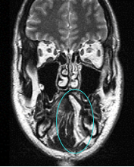

DTI fiber tracking shows IL fiber directions

Patient

Fiber directions:

Green: anterior-posterior

Blue: superior-inferior

Red: lateral-media

Tongue is outlined in yellow